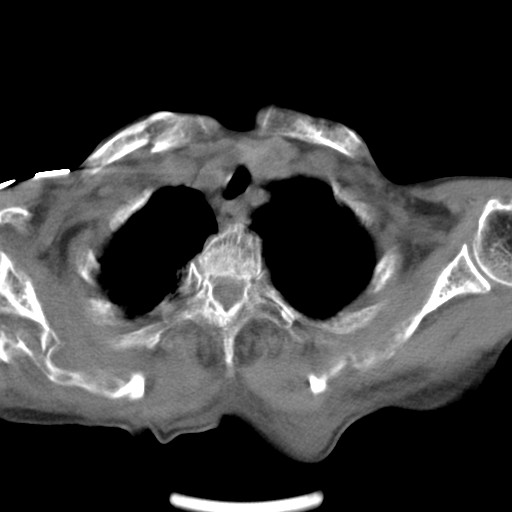

标题: CT21467:女,93岁,摔伤后检查。

女,93岁,摔伤后检查。

右肺炎症,心功能不全伴双侧胸腔积液,右下肺膨胀不全,食管裂孔疝,冠脉钙化,心包少量积液,左侧肋骨骨折,请上传骨窗.

右侧锁骨\\肩胛骨骨折、右侧湿肺,心功能不全伴双侧胸腔积液,右下肺膨胀不全,左膈破裂或食管裂孔疝,冠脉钙化,心包少量积液,请上传骨窗.

右肺炎症,心功能不全伴双侧胸腔积液,右下肺膨胀不全,食管裂孔疝,冠脉钙化,心包少量积液,左侧肋骨骨折,右肩甲骨粉碎性骨折。93岁,高寿哇!